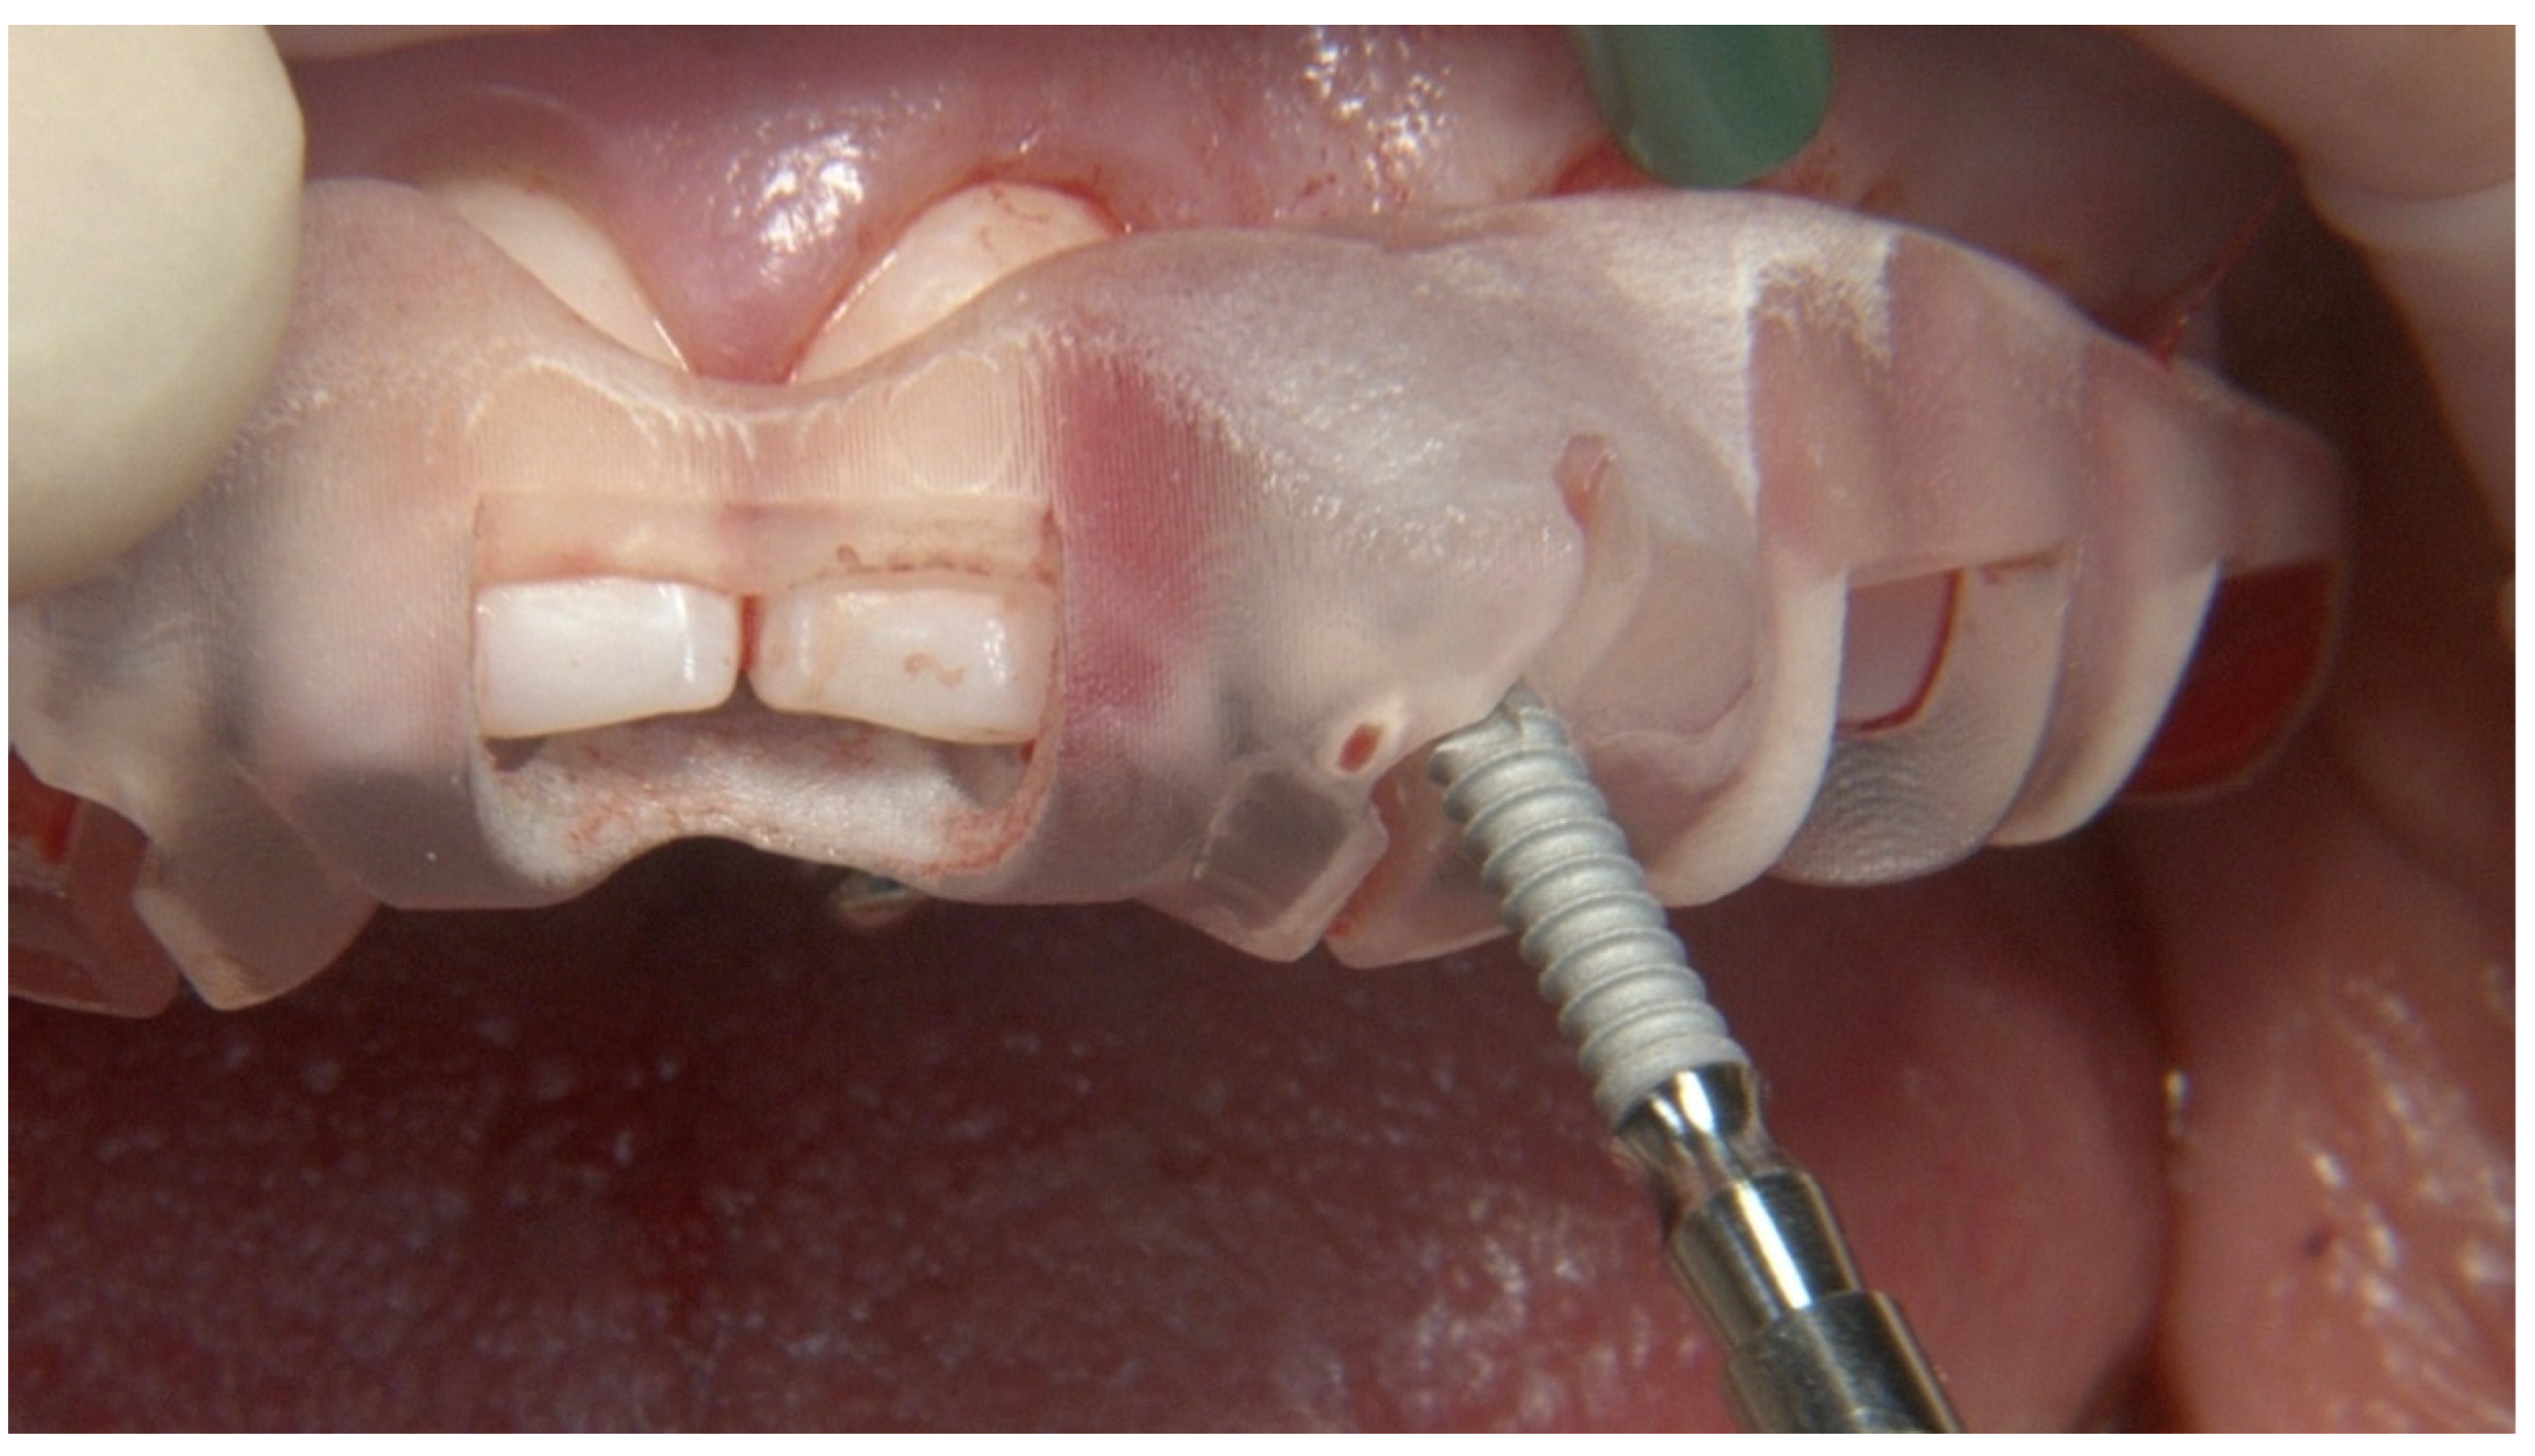

2.2. Surgical Protocol

2.3. Prosthetic Protocol